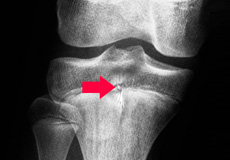

Growth Plate Fracture

Growth plates are areas of soft, cartilaginous tissues present at the end of long bones in growing children. These cartilage tissues or soft bones later harden to become solid bones in adulthood once growing has completed.